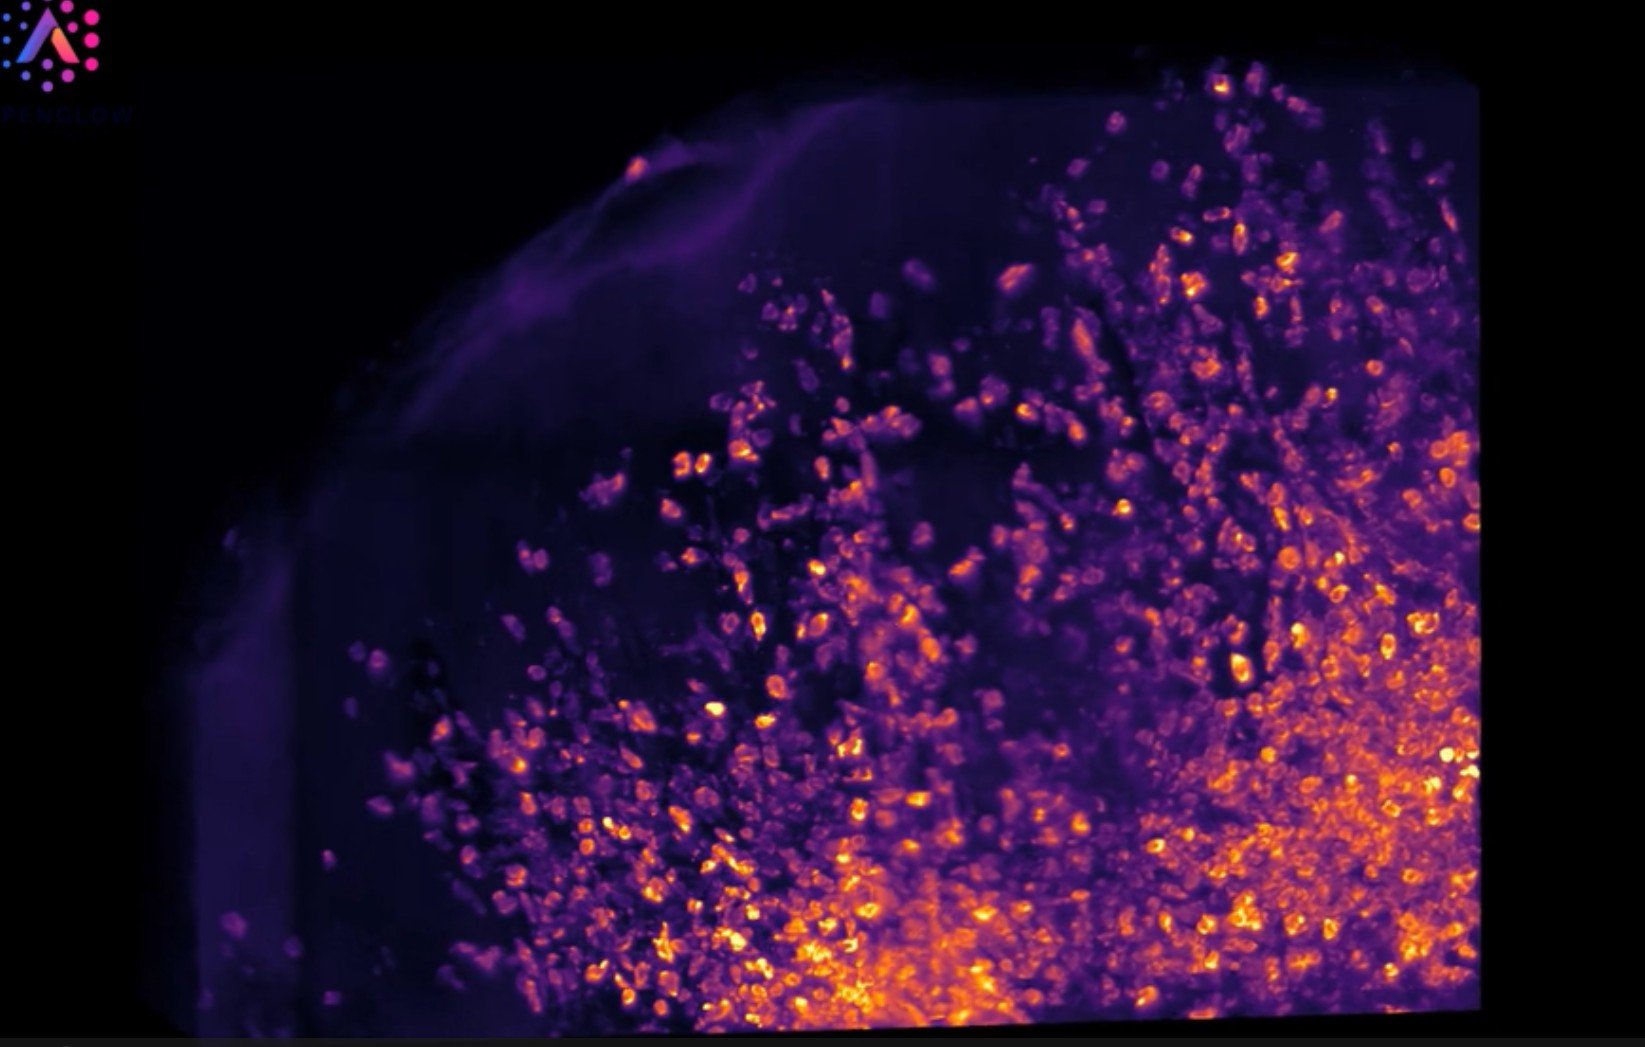

3D Imaging of Human Tonsil Tissue Highlighting Mast Cells with Tryptase Staining

3D view of human tonsil tissue stained with YO-PRO-1 and Tryptase, revealing mast cell distribution and spatial organization in unprecedented detail.